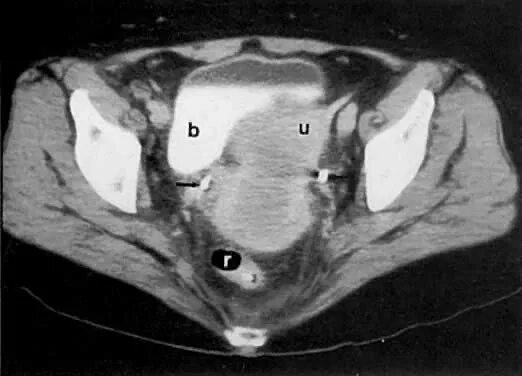

Метастазы в матке